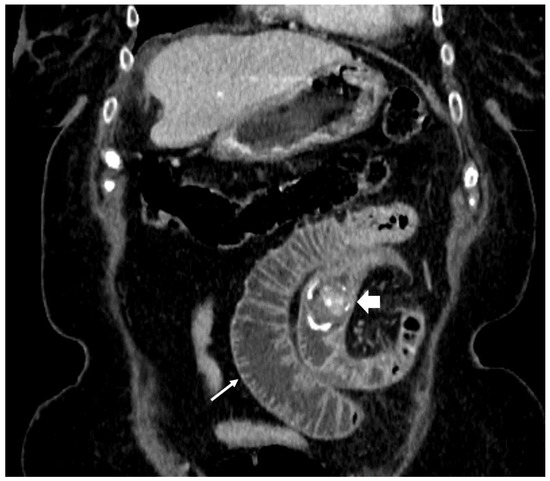

2. Case Presentation